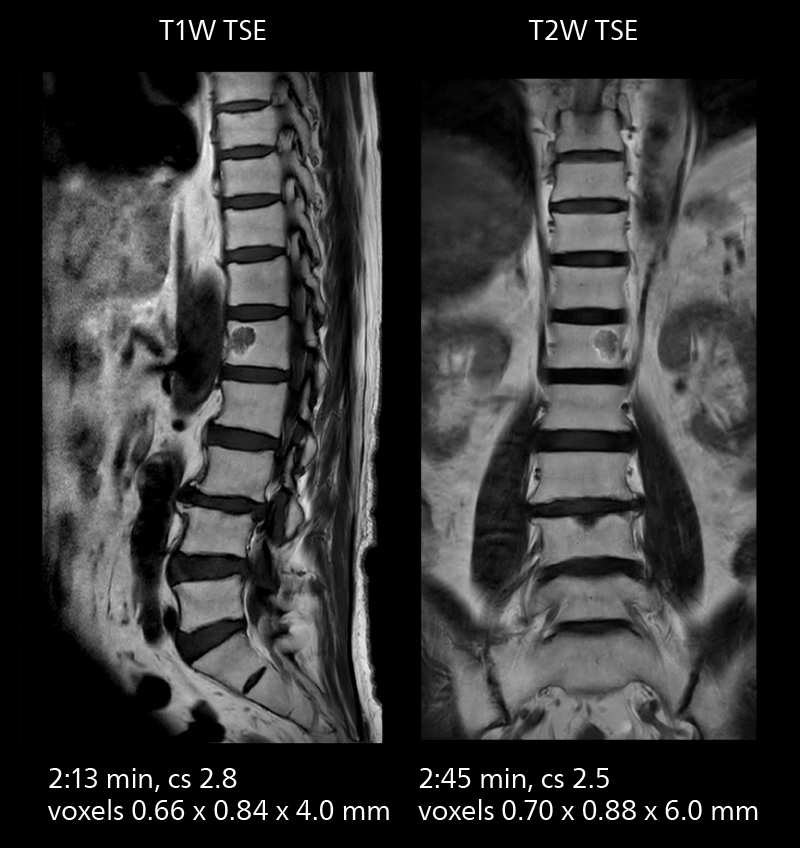

Lumbar spine MRI

Crisp images are obtained with high resolution and short scan times using Elition X. A cyst can be seen.